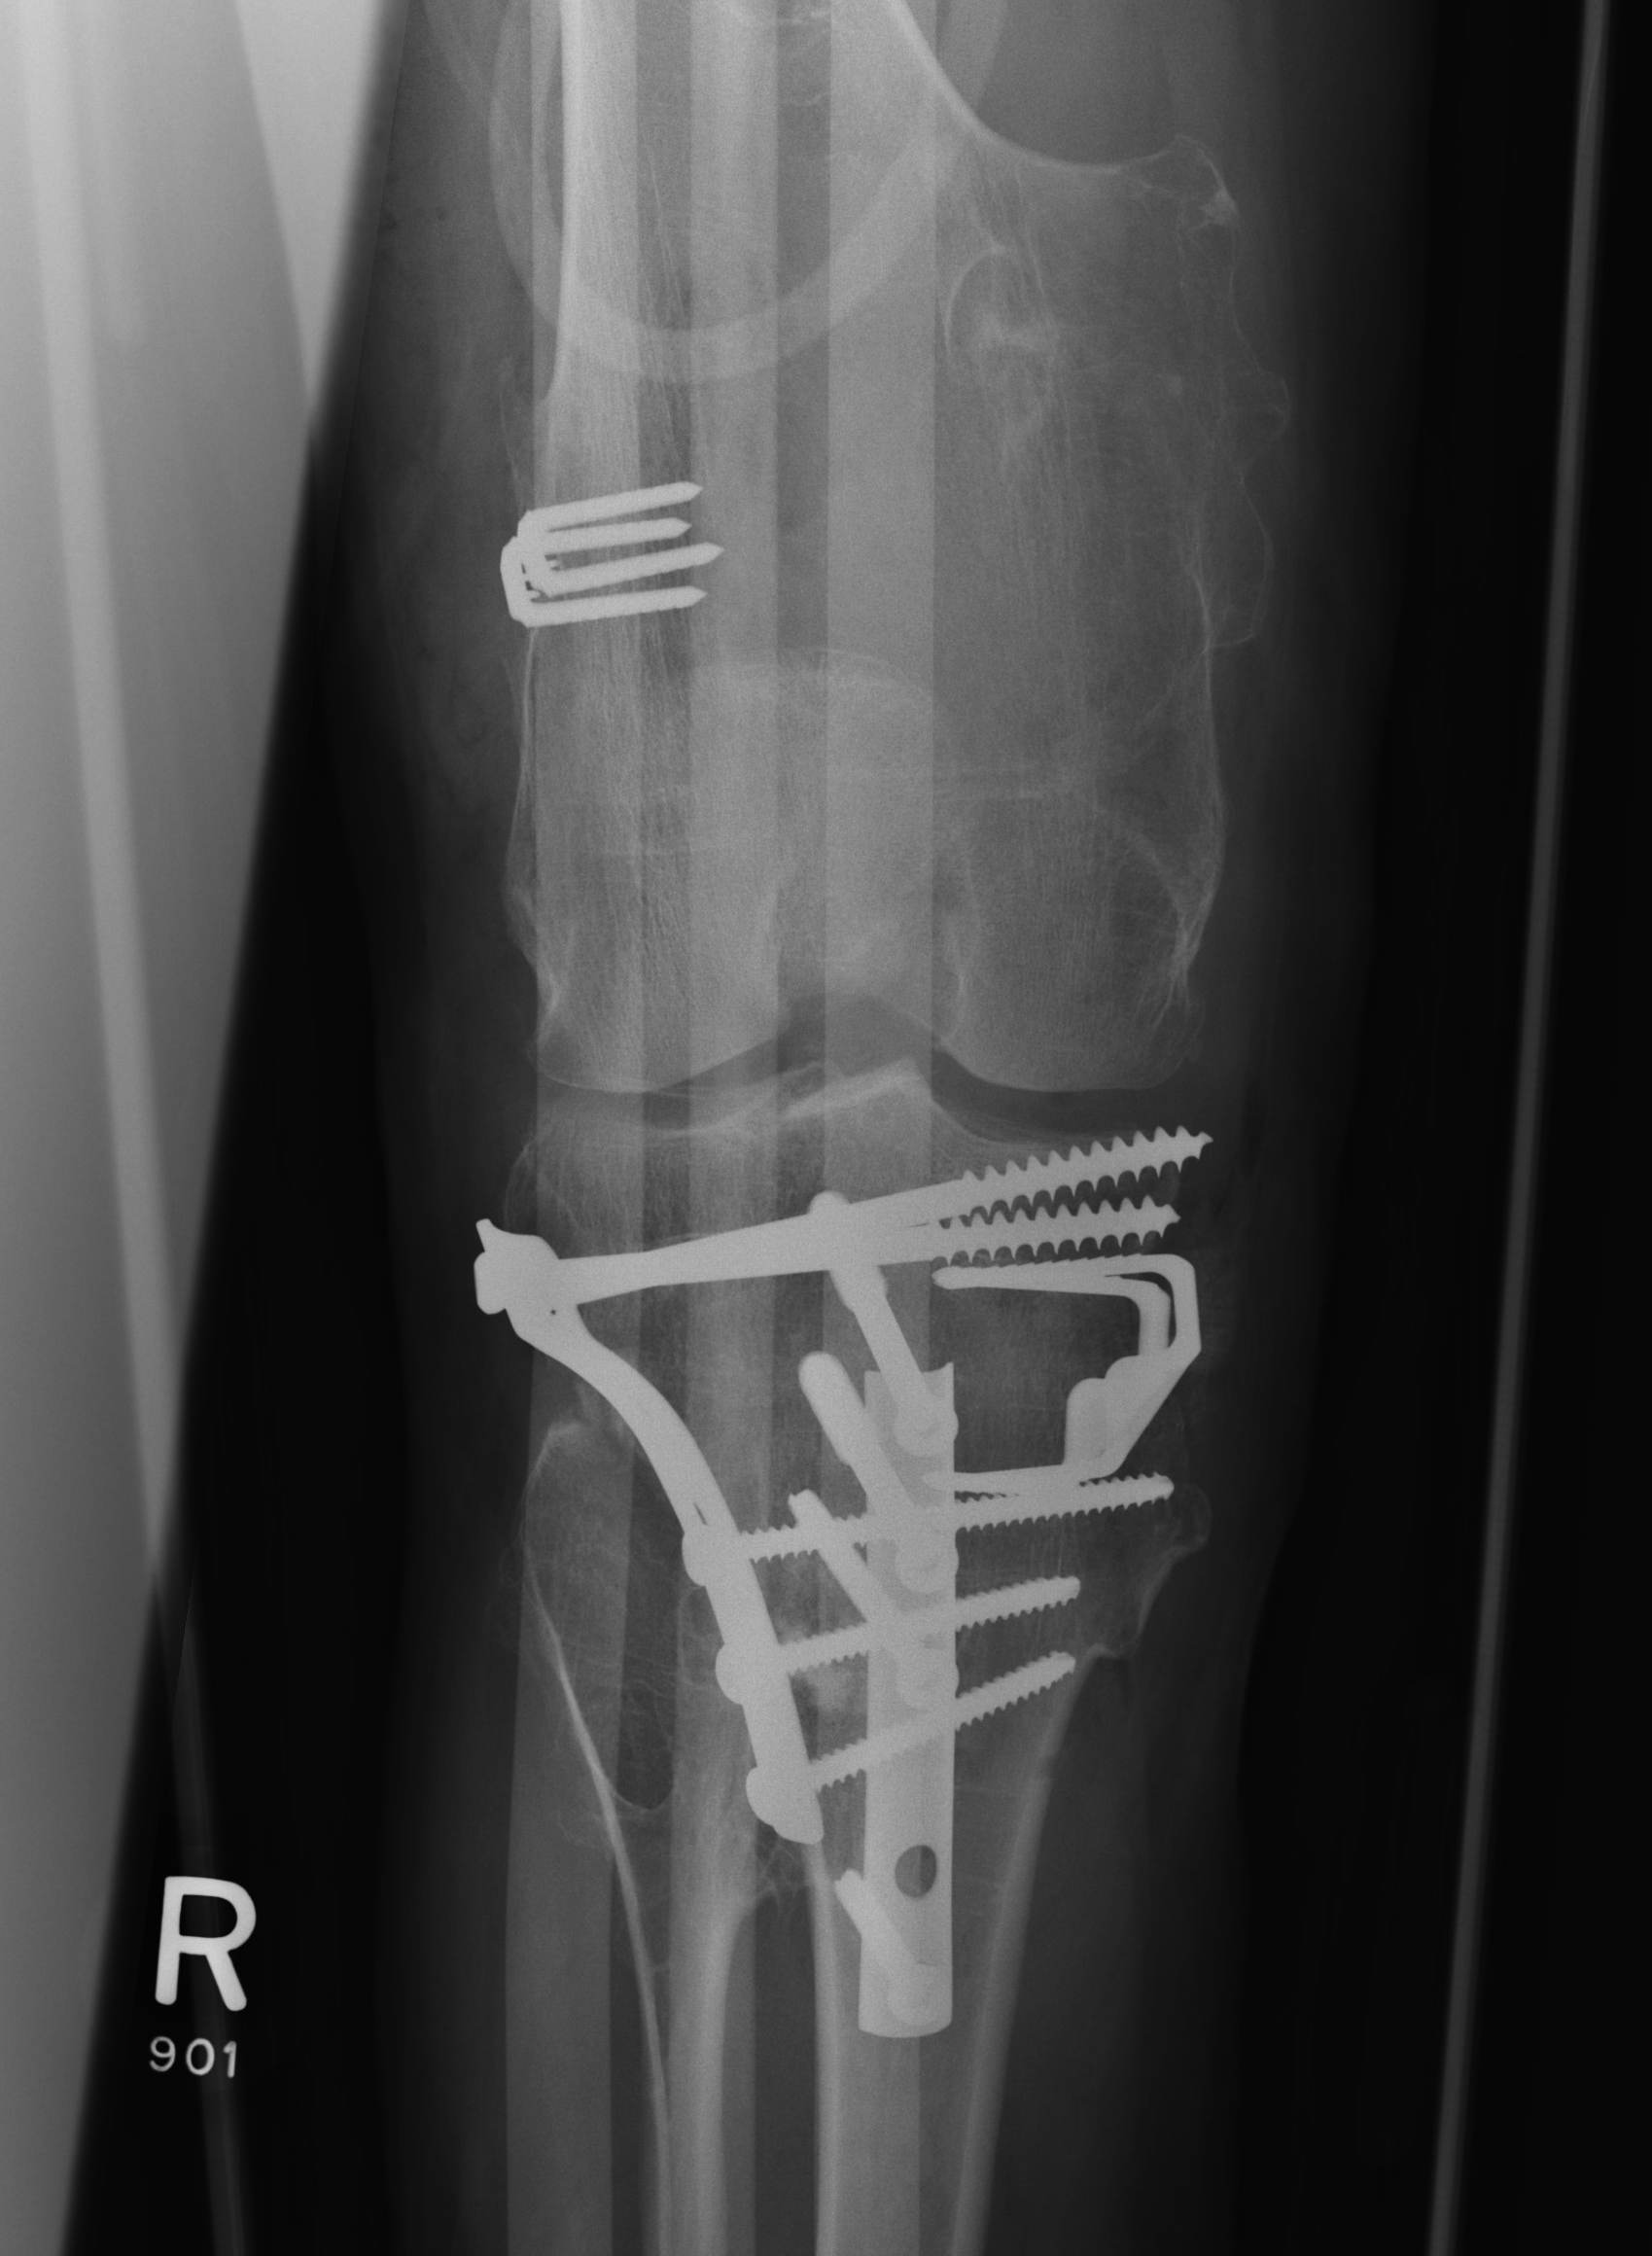

Osteotomy

Osteochondromas Valgus KneeOsteochondromas Knee Osteotomy 2Osteochondromas Knee Osteotomy AP

Kang et al J Paediatr Orthop 2017

- 15 cases of MHE with genu valgum

- treated with hemi-epiphyseal stapling

- 67% satisfactory corrections

- correction slower than idiopathic valgus correction (1.5 years v 1 year)